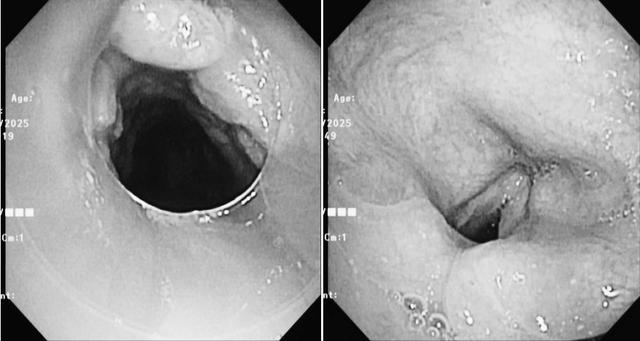

入院后,医疗团队为患者进行了无痛电子支气管镜检查,发现气管切开下方存在大量膜状肉芽组织,同时伴有声带明显水肿。这些病变严重阻碍了气道的通畅性,成为拔管困难的主要原因。

(▲支气管镜下声带息肉及气道狭窄情况)

(▲患者拔管前影像)

(▲患者拔管后影像)